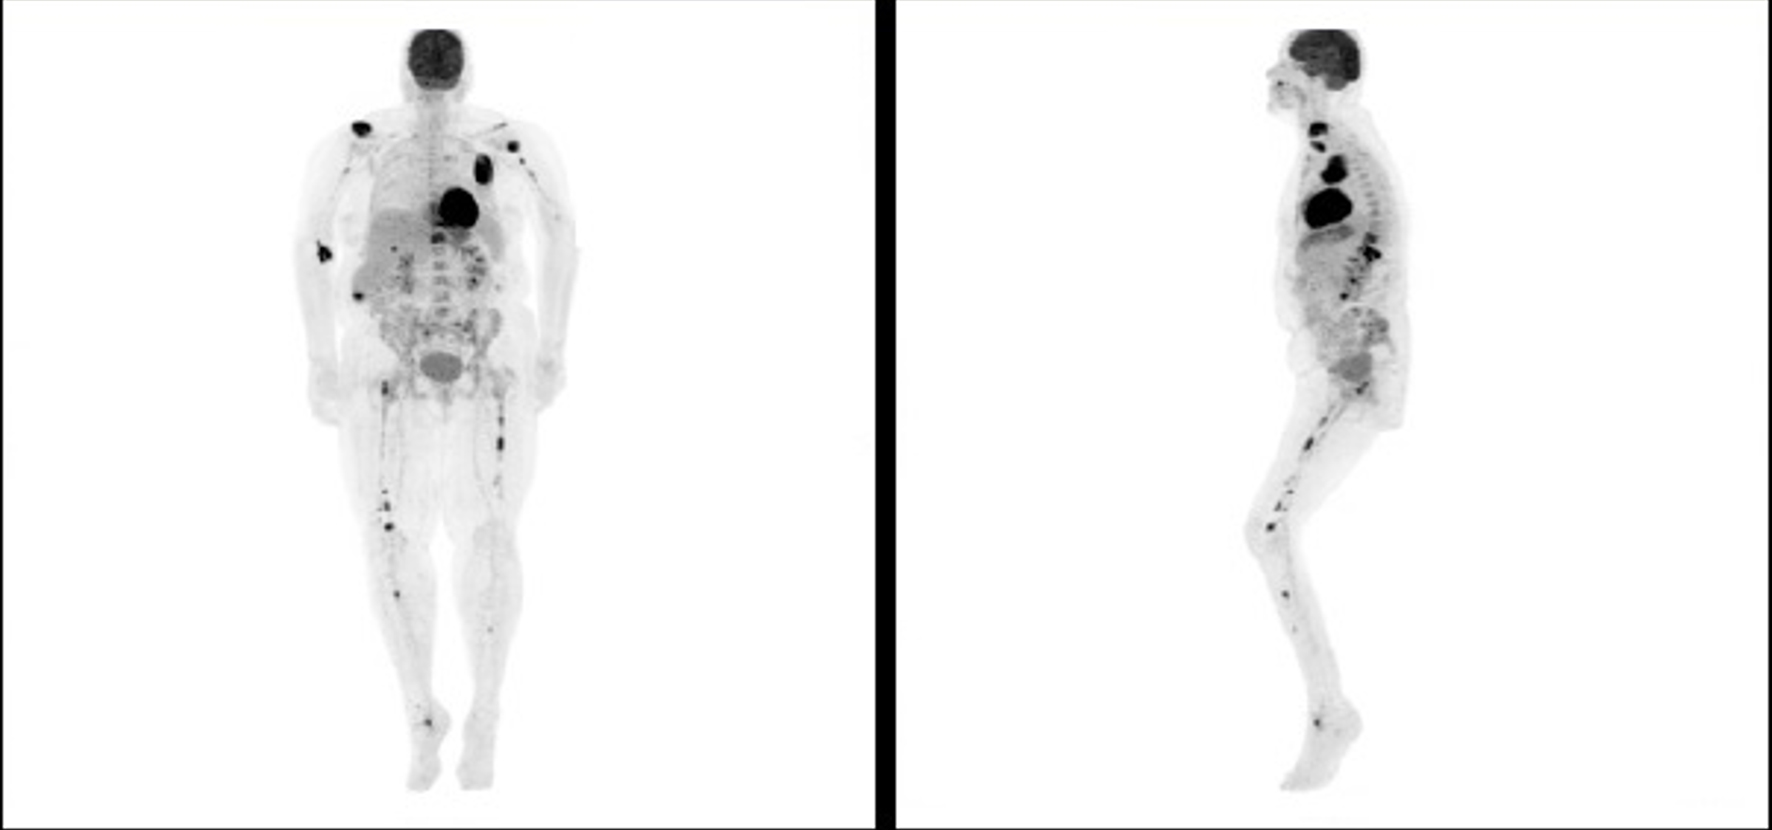

PET scan was repeated in January 2018 and showed interval development of several new FDG avid osseous lesions in the axial and appendicular skeleton as well as an incidentally detected intense hypodense lesion inferiorly in the posterior aspect of the right hepatic lobe with another small, but FDG avid focus more superiorly and medially in the posterior aspect of the right hepatic lobe. She was subsequently referred to an academic hospital by her primary oncologist due to progression of disease on PET (Figs. 1-3). Percutaneous biopsy of this newly identified liver lesion was performed from hepatic segment 6 and the pathology showed numerous abnormal plasmacytoid cells consistent with MM (Figs. 4 and 5). Interestingly, the patient did not have any symptoms or evidence of hepatomegaly on examination. Her liver function tests remained normal at the time of detection of the liver plasmacytoma and for the remainder of her disease course.

![]() Click for large image | Figure 1. Positron emission tomography scan showing progression of disease following initial chemotherapy. |

![]() Click for large image | Figure 2. Positron emission tomography scan at the time of relapse showing extraosseous and extramedullary involvement. |